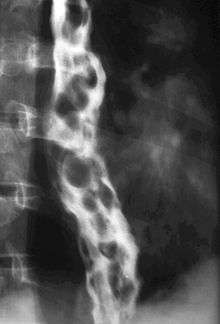

In medicine (gastroenterology), esophageal varices (or oesophageal varices) are extremely dilated sub-mucosal veins in the lower third[1] of the esophagus. They are most often a consequence of portal hypertension, commonly due to cirrhosis; patients with esophageal varices have a strong tendency to develop bleeding.

Pathogenesis

The upper two thirds of the esophagus is drained via the esophageal veins, which carry deoxygenated blood from the esophagus to the azygos vein, which in turn drains directly into the superior vena cava. These veins have no part in the development of esophageal varices. The lower one third of the esophagus is drained into the superficial veins lining the esophageal mucosa, which drain into the left gastric vein (coronary vein), which in turn drains directly into the portal vein. These superficial veins (normally only approximately 1 mm in diameter) become distended up to 1–2 cm in diameter in association with portal hypertension.

Normal portal pressure is approximately 9 mmHg compared to an inferior vena cava pressure of 2–6 mmHg. This creates a normal pressure gradient of 3–7 mmHg. If the portal pressure rises above 12 mmHg, this gradient rises to 7–10 mmHg.[3] A gradient greater than 5 mmHg is considered portal hypertension. At gradients greater than 10 mmHg, blood flow through the hepatic portal system is redirected from the liver into areas with lower venous pressures. This means that collateral circulation develops in the lower esophagus, abdominal wall, stomach, and rectum. The small blood vessels in these areas become distended, becoming more thin-walled, and appear as varicosities.

In situations where portal pressures increase, such as with cirrhosis, there is dilation of veins in the anastomosis, leading to esophageal varices. Splenic vein thrombosis is a rare condition that causes esophageal varices without a raised portal pressure. Splenectomy can cure the variceal bleeding due to splenic vein thrombosis.